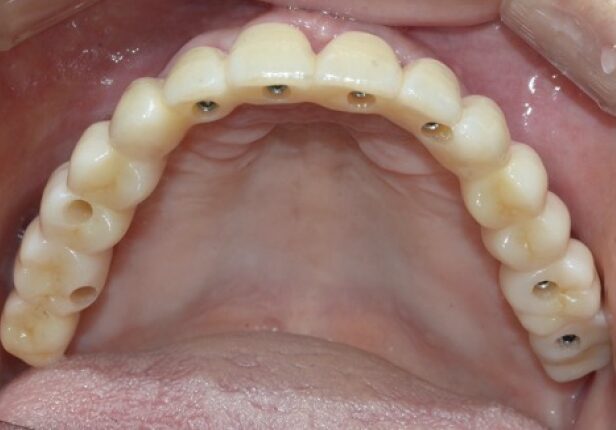

Coroa Final

caso de estudo